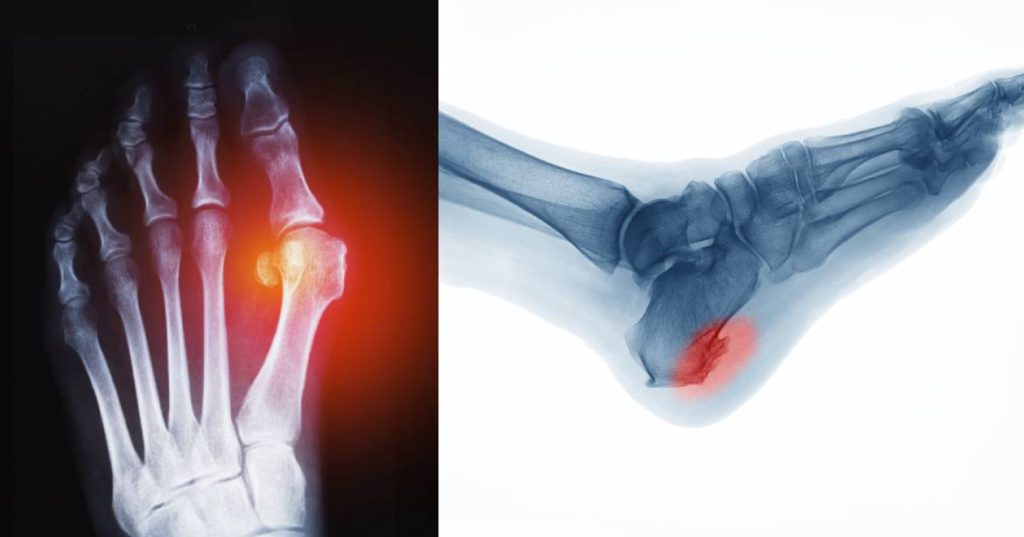

Bone Spur Surgery and Prevention Align Foot & Ankle How Invasive Is Bone Spur Surgery This minimally invasive procedure removes the affected disk and bone spurs through a small incision in the front of the neck. Your doctor made one or more small cuts called. There are several approaches to removing bone spurs, and your surgeon will choose the one best suited for your individual case. Some people with painful bone spurs due to osteoarthritis. How Invasive Is Bone Spur Surgery.